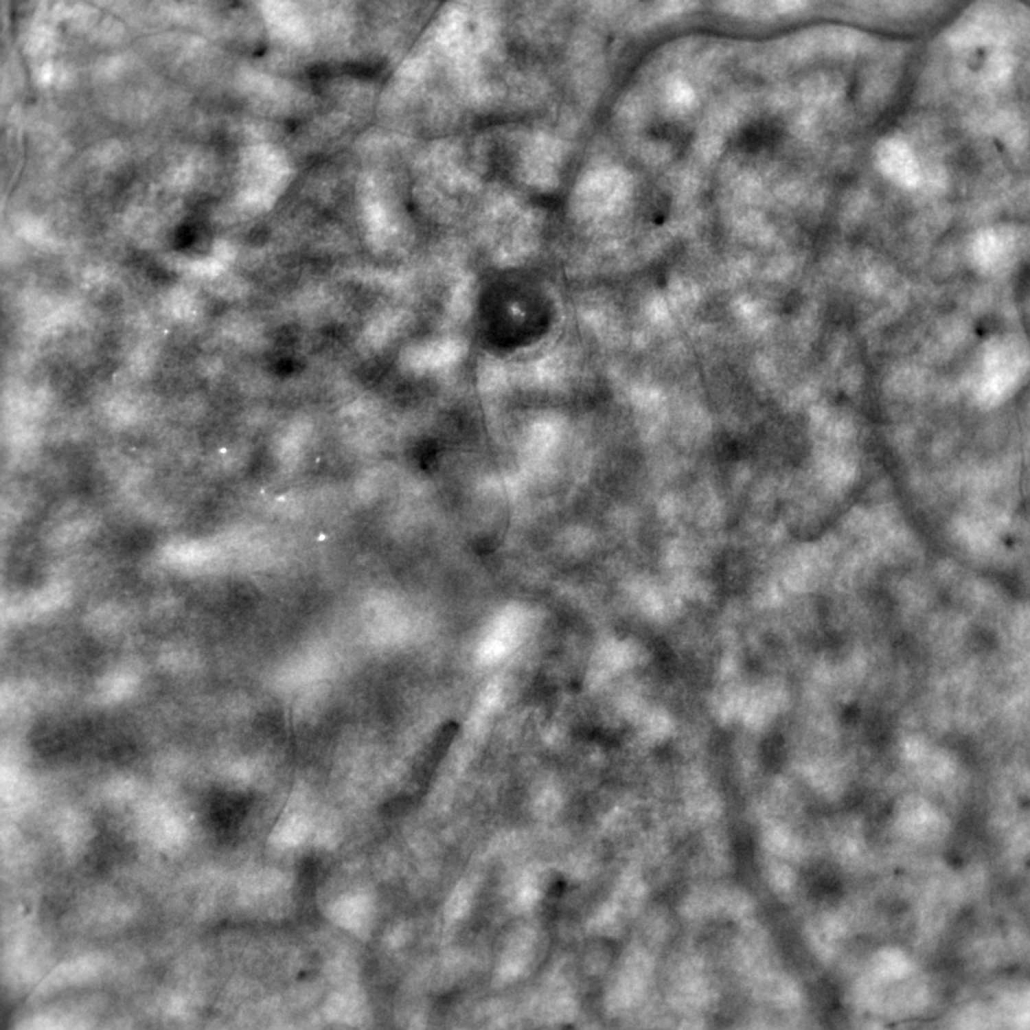

The TFI add-on module extends the imaging capability of rtx1 for investigating retinal anatomy, pathology and therapy. Using transscleral illumination, rtx1-TFI enables visualizations of otherwise invisible RPE cells and pigment redistribution in retinal degenerations.

AO examinations wiht rtx1-TFI are efficient, as a single acquisition delivers co-registered images of the cone mosaic and retinal pigment epithelium.